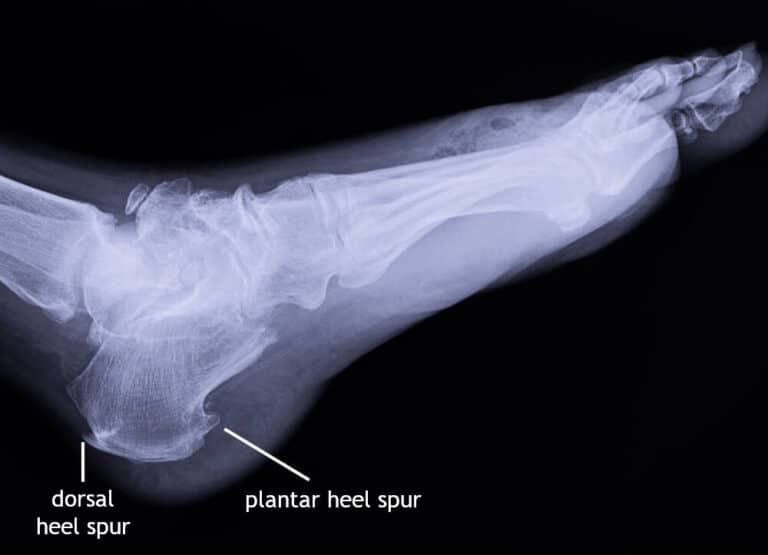

Calcaneal Spur Xray What Does Calcaneal Spur Mean A heel spur (also known as a calcaneal spur) is a bony outgrowth that you can sometimes see and feel on the underside of your foot. They are also known as calcaneal spurs or osteophytes. A heel spur is a calcium deposit causing a bony protrusion on the underside of the heel bone. A calcaneal spur, or commonly known as. What Does Calcaneal Spur Mean.

Calcaneal Spur Xray What Does Calcaneal Spur Mean A heel spur (also known as a calcaneal spur) is a bony outgrowth that you can sometimes see and feel on the underside of your foot. A calcaneal spur, or commonly known as a heel spur, occurs when a bony outgrowth forms on the heel bone. They are also known as calcaneal spurs or osteophytes. Calcaneal spurs can be located. What Does Calcaneal Spur Mean.

Calcaneal Spur Xray What Does Calcaneal Spur Mean A heel spur is a bony outgrowth that can occur on the underside of a person’s foot. Calcaneal spurs can be located at the back of the heel (dorsal heel spur) or under. A heel spur (also known as a calcaneal spur) is a bony outgrowth that you can sometimes see and feel on the underside of your foot. A. What Does Calcaneal Spur Mean.

Calcaneal Spur Xray What Does Calcaneal Spur Mean Calcaneal spurs can be located at the back of the heel (dorsal heel spur) or under. A heel spur (also known as a calcaneal spur) is a bony outgrowth that you can sometimes see and feel on the underside of your foot. A heel spur is a bony outgrowth that can occur on the underside of a person’s foot. A. What Does Calcaneal Spur Mean.